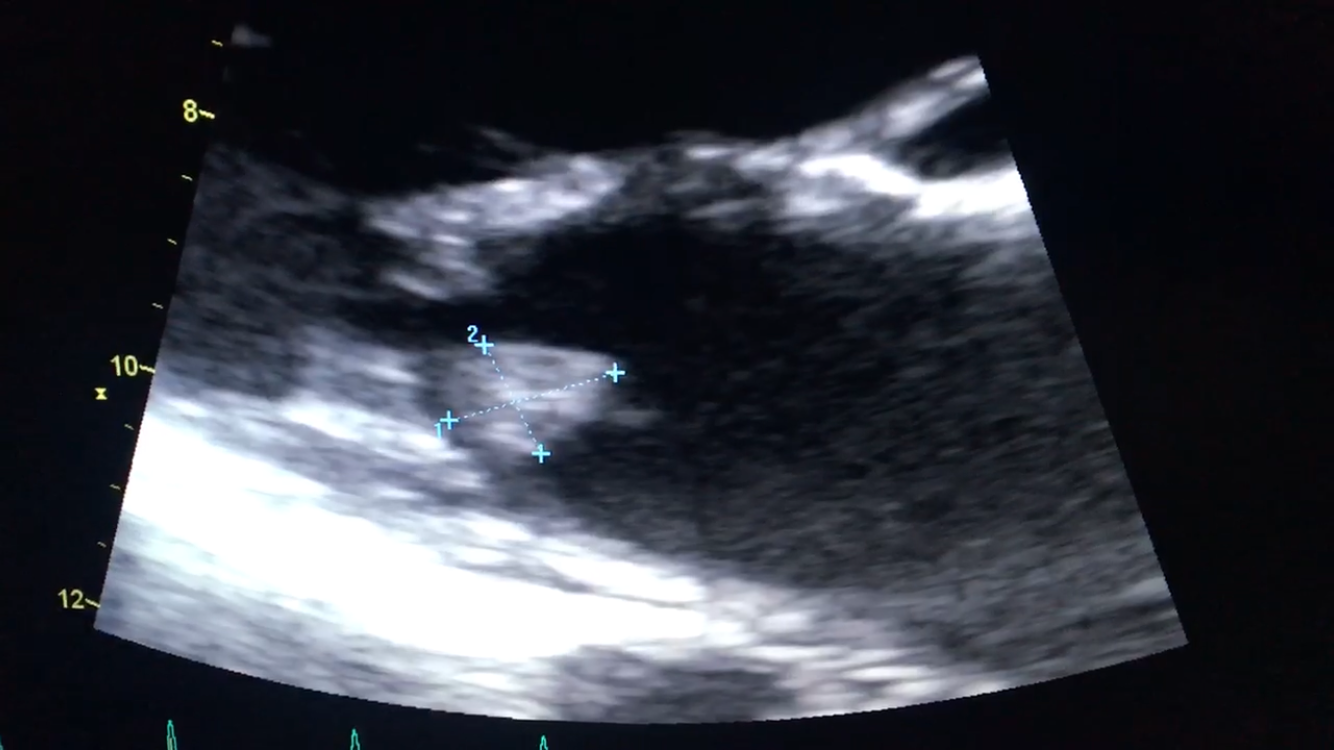

- Trans-esophageal echo [Fig 2,3] showed a mobile mass on the mitral valve. EF was 66% with normal LV function.

- On a 3-month follow up transthoracic echo, a new mass was seen on the posterior leaflet of the mitral valve [Fig 8]. The mass resolved after 4 days of anticoagulation.